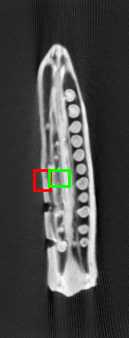

The dataset from this longitudinal medical study consists of 8 scans taken during the ablation procedure. We demonstrate our method for 2D reconstruction by choosing a single slice from each of the 8 volumes as our dataset. Note that all these 8 slices are located at the same index 222The notion of same index (slice number corresponding to the same depth) makes sense in the context, because in such problems, the different scans are aligned with each other. within each of the respective volumes. Fig. 3 shows the chosen set of 2D slices (each of size ) from the different volumes. Observe that the needle is seen in all of the first 7 slices and the effect of ablation is seen in the 8th slice.

Tracking the needle: We first choose slices 1-6 as our templates, and reconstruct slice 7 with the specific goal of tracking the needle and simultaneously reduce artefacts. Fig. 4 shows the reconstruction of slice 7 from its measurements from only 90 views. The reconstructions are quantitatively compared using SSIM.

Observing details of the ablation: Next, we choose slices 1-7 as our templates and reconstruct slice 8 from 120 views i.e., a somewhat higher number of views this time. Fig. 5 shows the reconstructions of slice 8 by different methods. We see that the weighted prior reconstruction brings in the advantage of the prior without it adversely affecting the new regions.